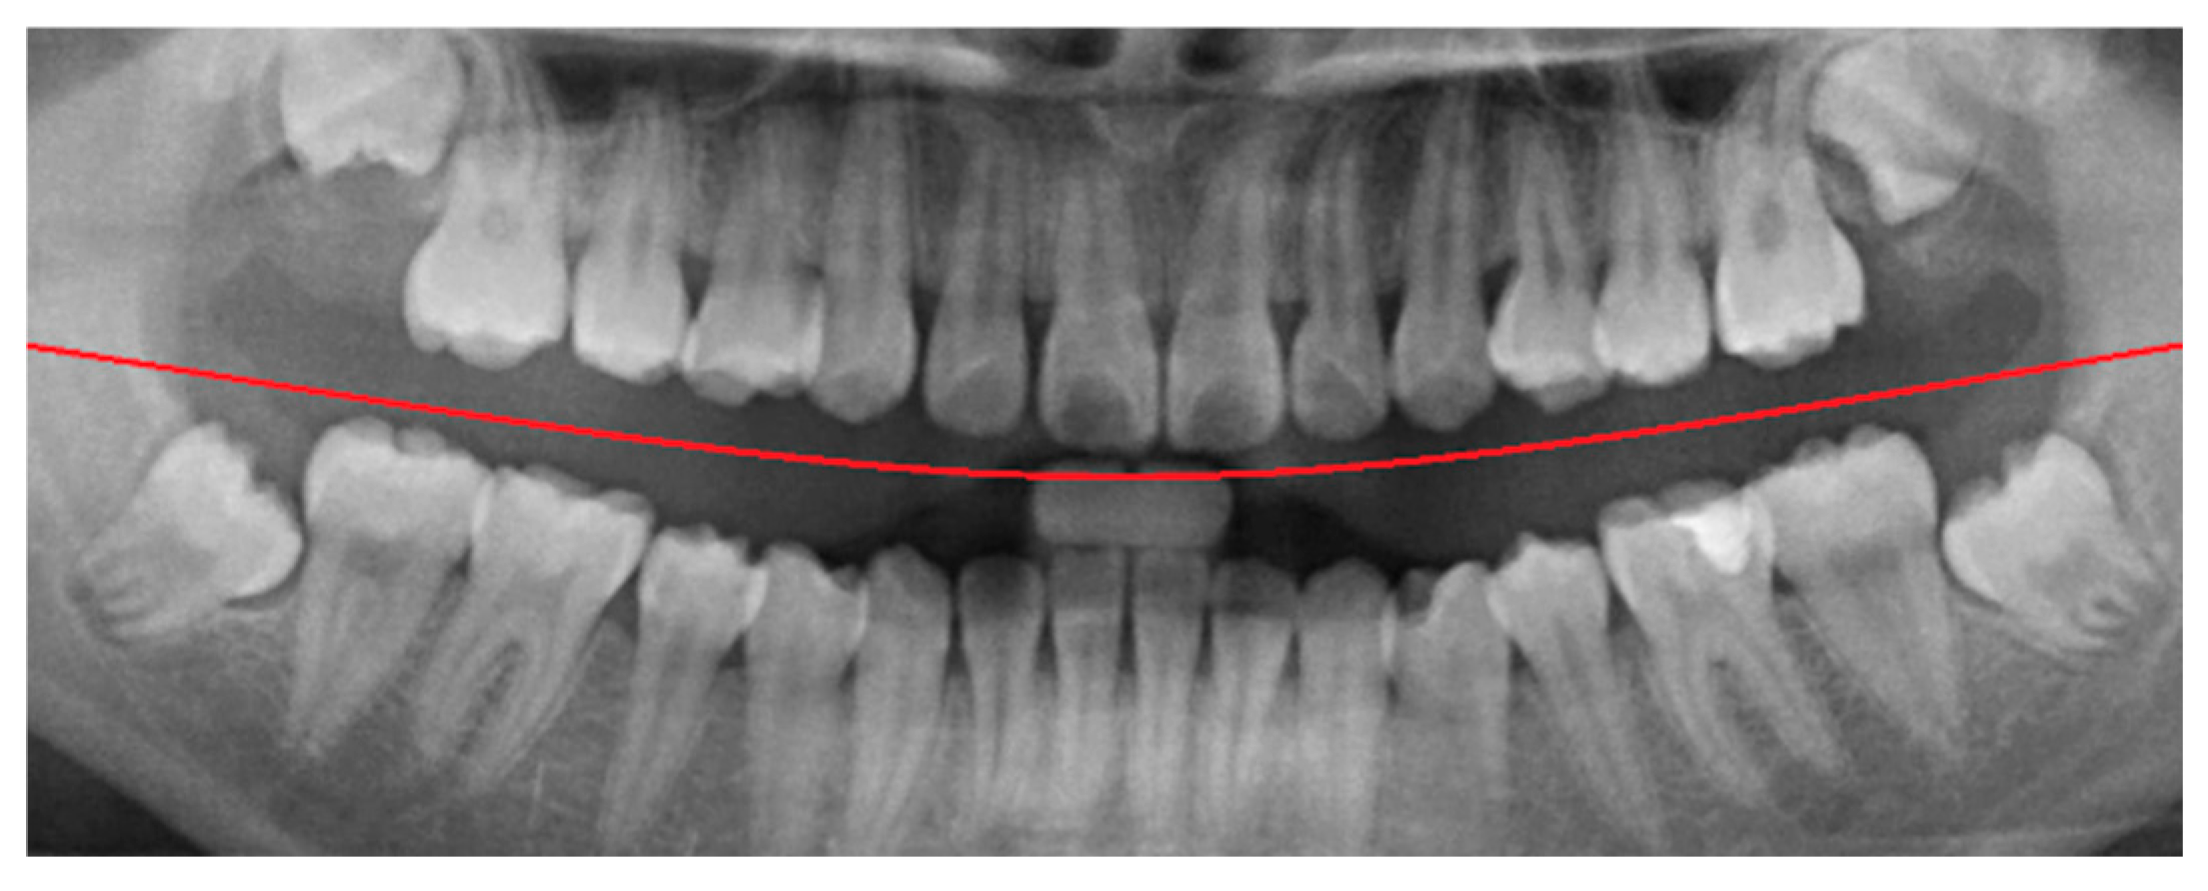

To minimize the influence of non-target regions on the recognition process, position adjustment was implemented as a critical preprocessing step. Given the variability in oral cavity positioning across different patients, the average location of the oral cavity was estimated using 100 randomly selected PANO images. Based on this analysis, the target region was determined to be approximately 625 × 1650 pixels, as shown in Figure 3. Using this reference region, only the relevant portions of each original PANO image were retained. This cropping process effectively eliminated extraneous areas outside the alveolar bone, thereby enhancing the accuracy and efficiency of the subsequent recognition tasks performed by the CNN model.

Figure 3. An example of finding the initial average block. (a) The original PANO image with the red line representing the ideal cropping line. (b) The result of position adjustment.